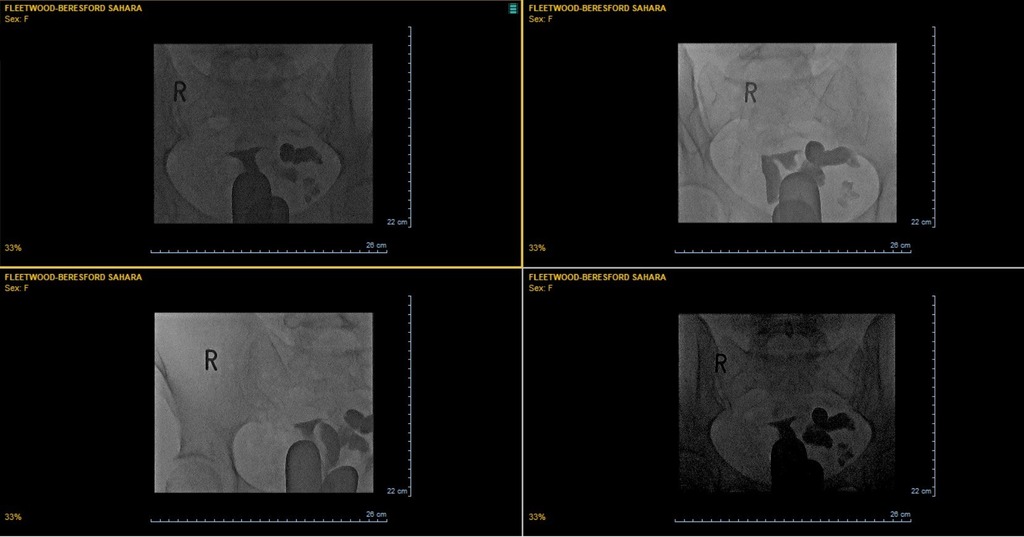

#FertilityTesting journey | #Hysterosalpingogram and further blood tests 🔗 ift.tt/GbY6gKE 🩸 A Hysterosalpingogram (HSG) is an X-ray procedure that is used to view the inside of the uterus and fallopian tubes. A catheter is inserted through… instagr.am/p/CzRdzSJpLhc/

A Hysterosalpingogram (HSG) is an X-ray procedure that is used to view the inside of the uterus and fallopian tubes. A catheter is inserted through… instagr.am/p/CzRdzSJpLhc/

#FertilityTesting journey | #Hysterosalpingogram X-ray 🔗 ift.tt/xIDCulR I was up early to get showered ahead of the appointment. I’ll be honest, I was dreading it; remembering the pain of the dilation. The nurse collected me, asked me to pee… instagr.am/p/Czbz9eiIKXa/

I was up early to get showered ahead of the appointment. I’ll be honest, I was dreading it; remembering the pain of the dilation.

The nurse collected me, asked me to pee… instagr.am/p/Czbz9eiIKXa/

#FertilityTesting journey | #Hydrosalpinges and hormone problems 🔗 ift.tt/4XndGUg The results of the #Hysterosalpingogram (HSG) are in. It clearly shows that my left fallopian tube is blocked and filled with fluid. This is called a #hydrosalpiinstagr.am/p/CzeUoPIt0-d/

The results of the #Hysterosalpingogram (HSG) are in. It clearly shows that my left fallopian tube is blocked and filled with fluid. This is called a #hydrosalpi… instagr.am/p/CzeUoPIt0-d/